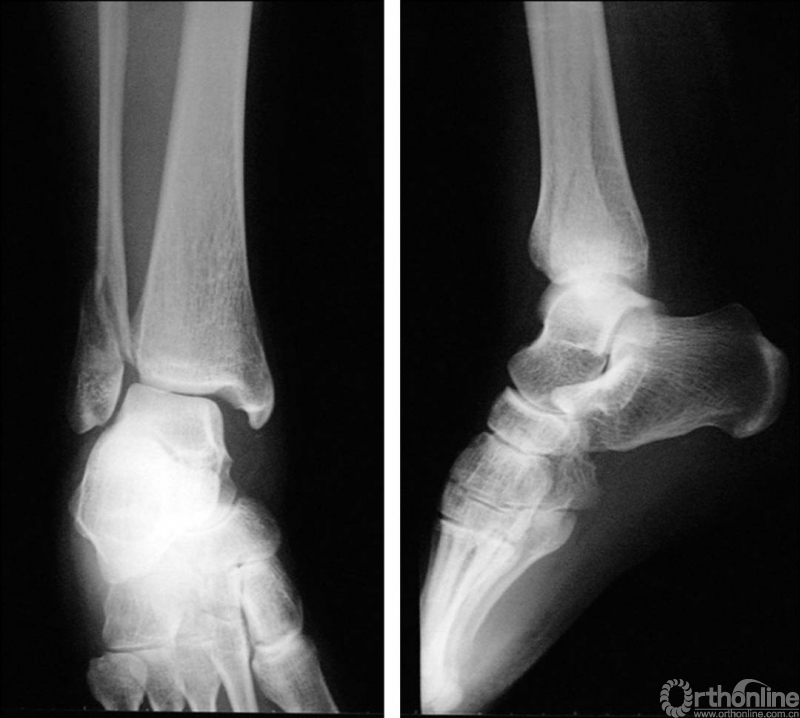

X线诊断:标准的踝关节影像学评估应包括3个位相:前后位(图5),踝穴位(内旋15°)(图6),侧位(图7)。

图5 前后位

图6 踝穴位(内旋15°)

当踝关节严重损伤时内外踝及距骨将发生不同程度的移位(图8)。有时外踝骨折会伴有三角韧带的损伤,静态的X线摄片并不能准确地反映踝关节的稳定性,应力位片及MRI检查可完善对踝关节稳定性及韧带损伤的评估(图9)。此时应通过患肢损伤机制及放射资料准确判断踝关节损伤的类型以正确指导复位和固定。有时单纯内踝骨折可能是更为复杂的“Maisonneuve骨折”的一部分,该骨折还包括腓骨近端骨折及韧带联合损伤,故X线检查应投照整个胫腓骨。

图8 骨折移位明显合并有脱位

图9 应力位X线片(三角韧带断裂)